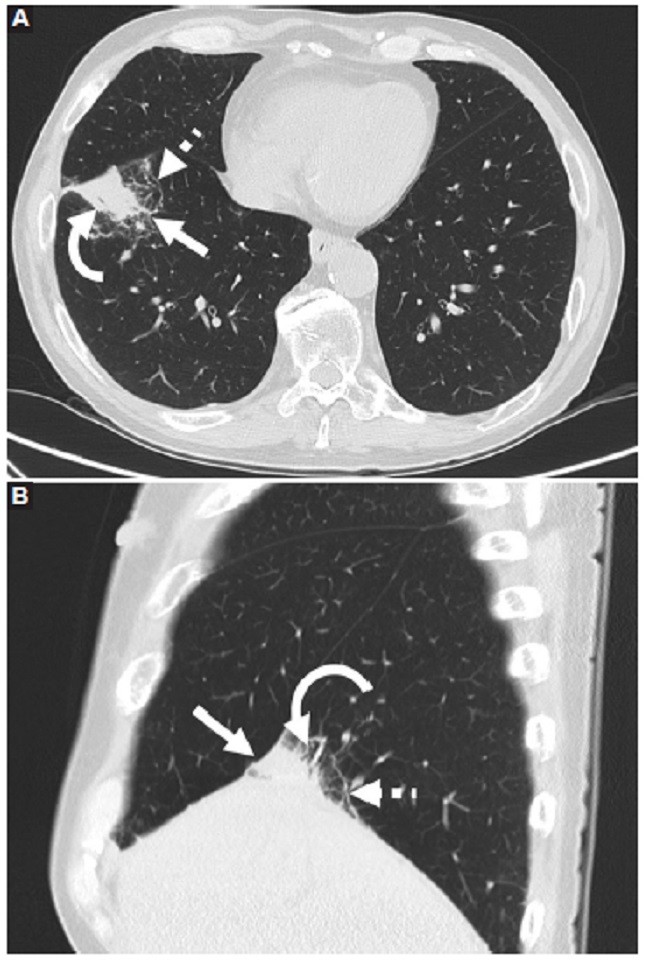

Presentamos el caso de un hombre de 67 años con diagnóstico reciente de carcinoma epidermoide queratinizante orofaríngeo, que en TC y PET-TC de estadificación presentó imagen pulmonar, consolidativa, en contacto con la cisura mayor y el domo diafragmático, con fino broncograma aéreo y reticulación perilesional (Fig. 1). Esta lesión demostró ser hipermetabólica con un SUV de 5,5 (Fig. 2). Dados los hallazgos, se realizó biopsia percutánea guiada por TC para confirmar secundarismo. Sin embargo, se identificó infiltración por población linfocitaria B de pequeño tamaño con perfil inmunohistoquímico positivo para CD20, bcl2 y Kappa, resultando negativo con CD3, CD5, Ciclina D1, CD10 y Lambda (Fig. 3). La citometría de flujo arrojó linfocitos B: 45,32%, población patológica: 96,06%, CD19+, CD20+, CD10-, CD5-, kappa+, CD23-, y CD43+ débil. Se arribó entonces al diagnóstico de infiltración por linfoma B de la zona marginal extraganglionar (MALT). Realizó tratamiento de inducción con esquema docetaxel, 5-fluouracilo y cisplatino. Luego consolidación con radioterapia y carboplatino concurrente. En la nueva PET-TC, seis meses más tarde, se pudo apreciar disminución de la captación de 18-fluorodesoxiglucosa (18F-FDG) y del tamaño de la lesión pulmonar (Fig. 4).

Con respecto a la presentación en TC, esta entidad adquiere varias formas: consolidaciones, masas y/o nódulos. Se puede asociar a áreas de reticulación, infiltrados peribronquiales y/o broncograma aéreo6,7. El LBALT raramente presenta áreas de cavitación, engrosamiento pleural, derrame pleural o infiltración linfangítica8,9. Asimismo, no suele asociarse a adenopatías mediastinales o hiliares9. Deng et al. (2 encontraron que el formato de presentación más común fue el de consolidación (62%) seguido de nódulos (43%). En forma adicional, describieron que pueden existir formatos mixtos de presentación en los que la consolidación y los nódulos, en conjunto, fueron los hallazgos más frecuentes (13%). Sin embargo, la presentación más frecuente es con formato simple2. La afección puede ser unilateral o bilateral2,7. El realce luego de la inyección de contraste iodado endovenoso es similar al de otras lesiones pulmonares malignas2. Cabe destacar que estas lesiones pueden o no presentar captación de 18F-FDG en PET-TC. En todo caso, la captación suele ser leve y no patognomónica6,9. Sin embargo, la PET-TC puede ser útil para la detección de LBALT, debido a la escasa actividad metabólica pulmonar3,8. Dentro de los diagnósticos diferenciales imagenológicos se encuentran el carcinoma broncoalveolar, amiloidosis, hiperplasia linfoide, granulomatosis de Wegner, neumonía criptogénica o proceso infeccioso. La estabilidad en los sucesivos controles imagenológicos acercan al diagnóstico de LBALT6. El diagnóstico de certeza se logra mediante estudio histológico asistido por inmunofenotipificación para distinguirlo de otros linfomas no Hodgkin de bajo grado.